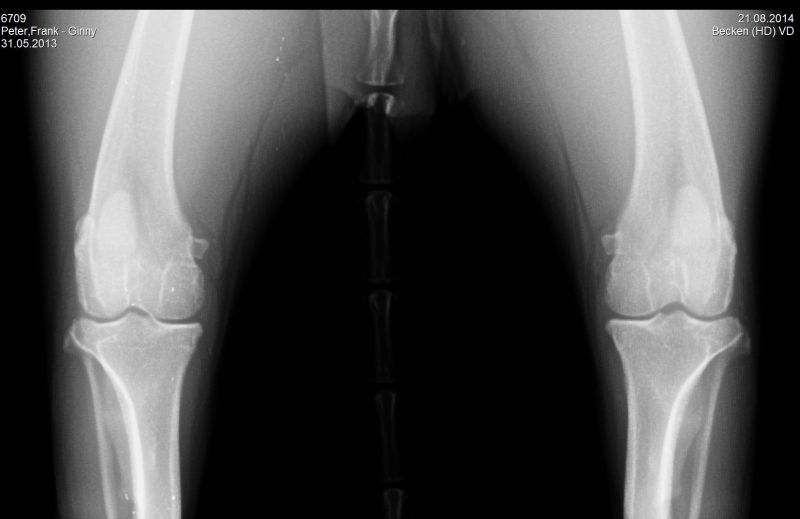

21.08.2014 - Ginny HD-und ED geröntgt - 15 Monate alt

24.08.2014 - Ginny - 15 Monate alt